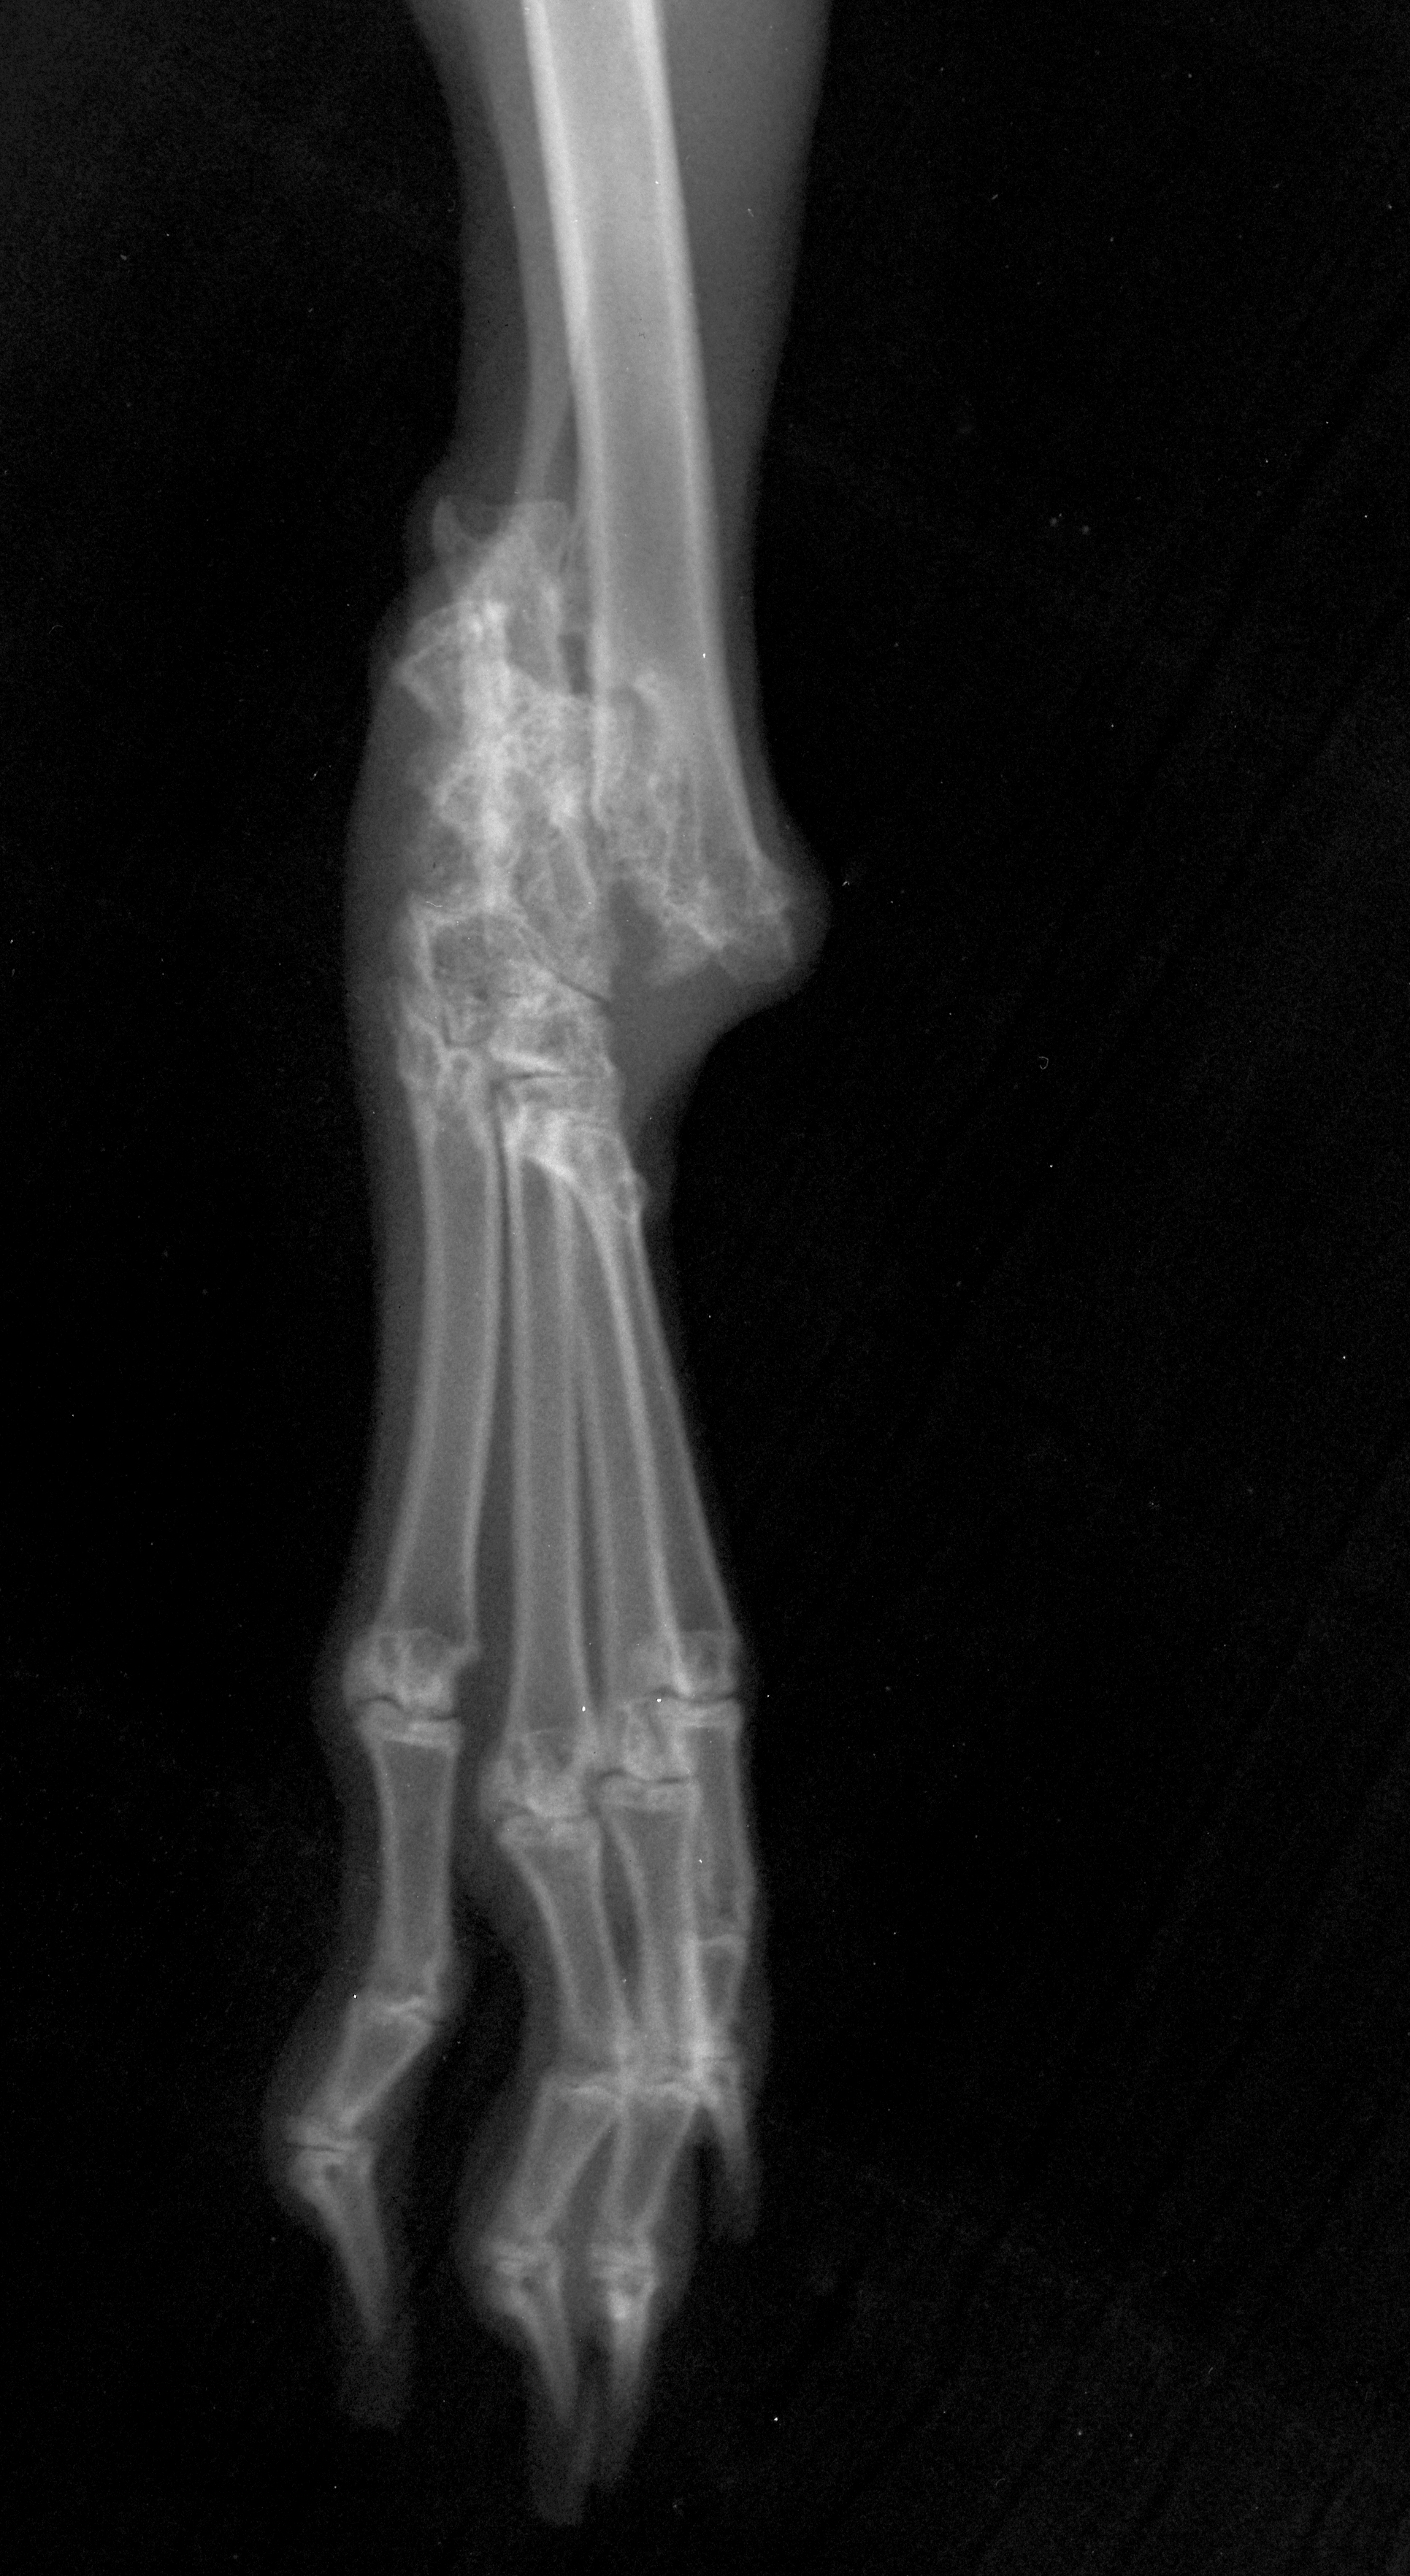

Jack's hock

Jack with fractured leg

Jack VD fractured hock